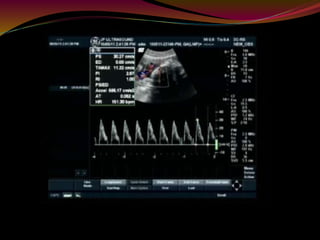

UMBILICAL ARTERY

 Umbilical arterial (UA) Doppler assessment is

used in surveillance of fetal well-being in the third

trimester of pregnancy.

 Abnormal umbilical artery Doppler is a marker

of uteroplacental insufficiency and

consequent intrauterine growth restriction (IUGR) or

suspected pre-eclampsia.

 Doppler ultrasound

 The Doppler indices measured at the fetal end the

free loop and the placental end of the umbilical cord

are different with the impedance highest at the fetal

end.

 The changes in the indices are likely to be seen at the

fetal end first. Ideally the measurements should be

made in the free cord.

Waveform

 “Saw tooth" pattern with flow always in the forward

direction.

 An abnormal waveform shows absent or reversed

diastolic flow.